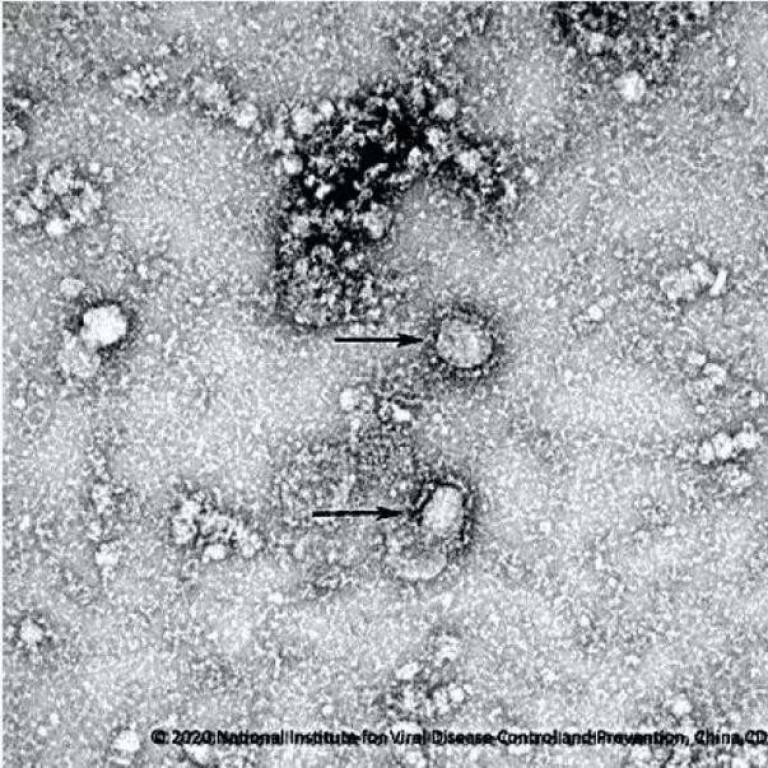

(UTV| சீனா) – சீனாவில் பரவிய கொரோனா வைரஸ் இற்றைக்கு வேகமாகப் பரவி வரும் நிலையில், தற்போது சீன சுகாதாரத் துறை அதிகாரிகள் கொரோனா வைரஸின் நுண்ணிய படங்களை வெளியிட்டுள்ளனர்.

குறித்த படங்கள்..